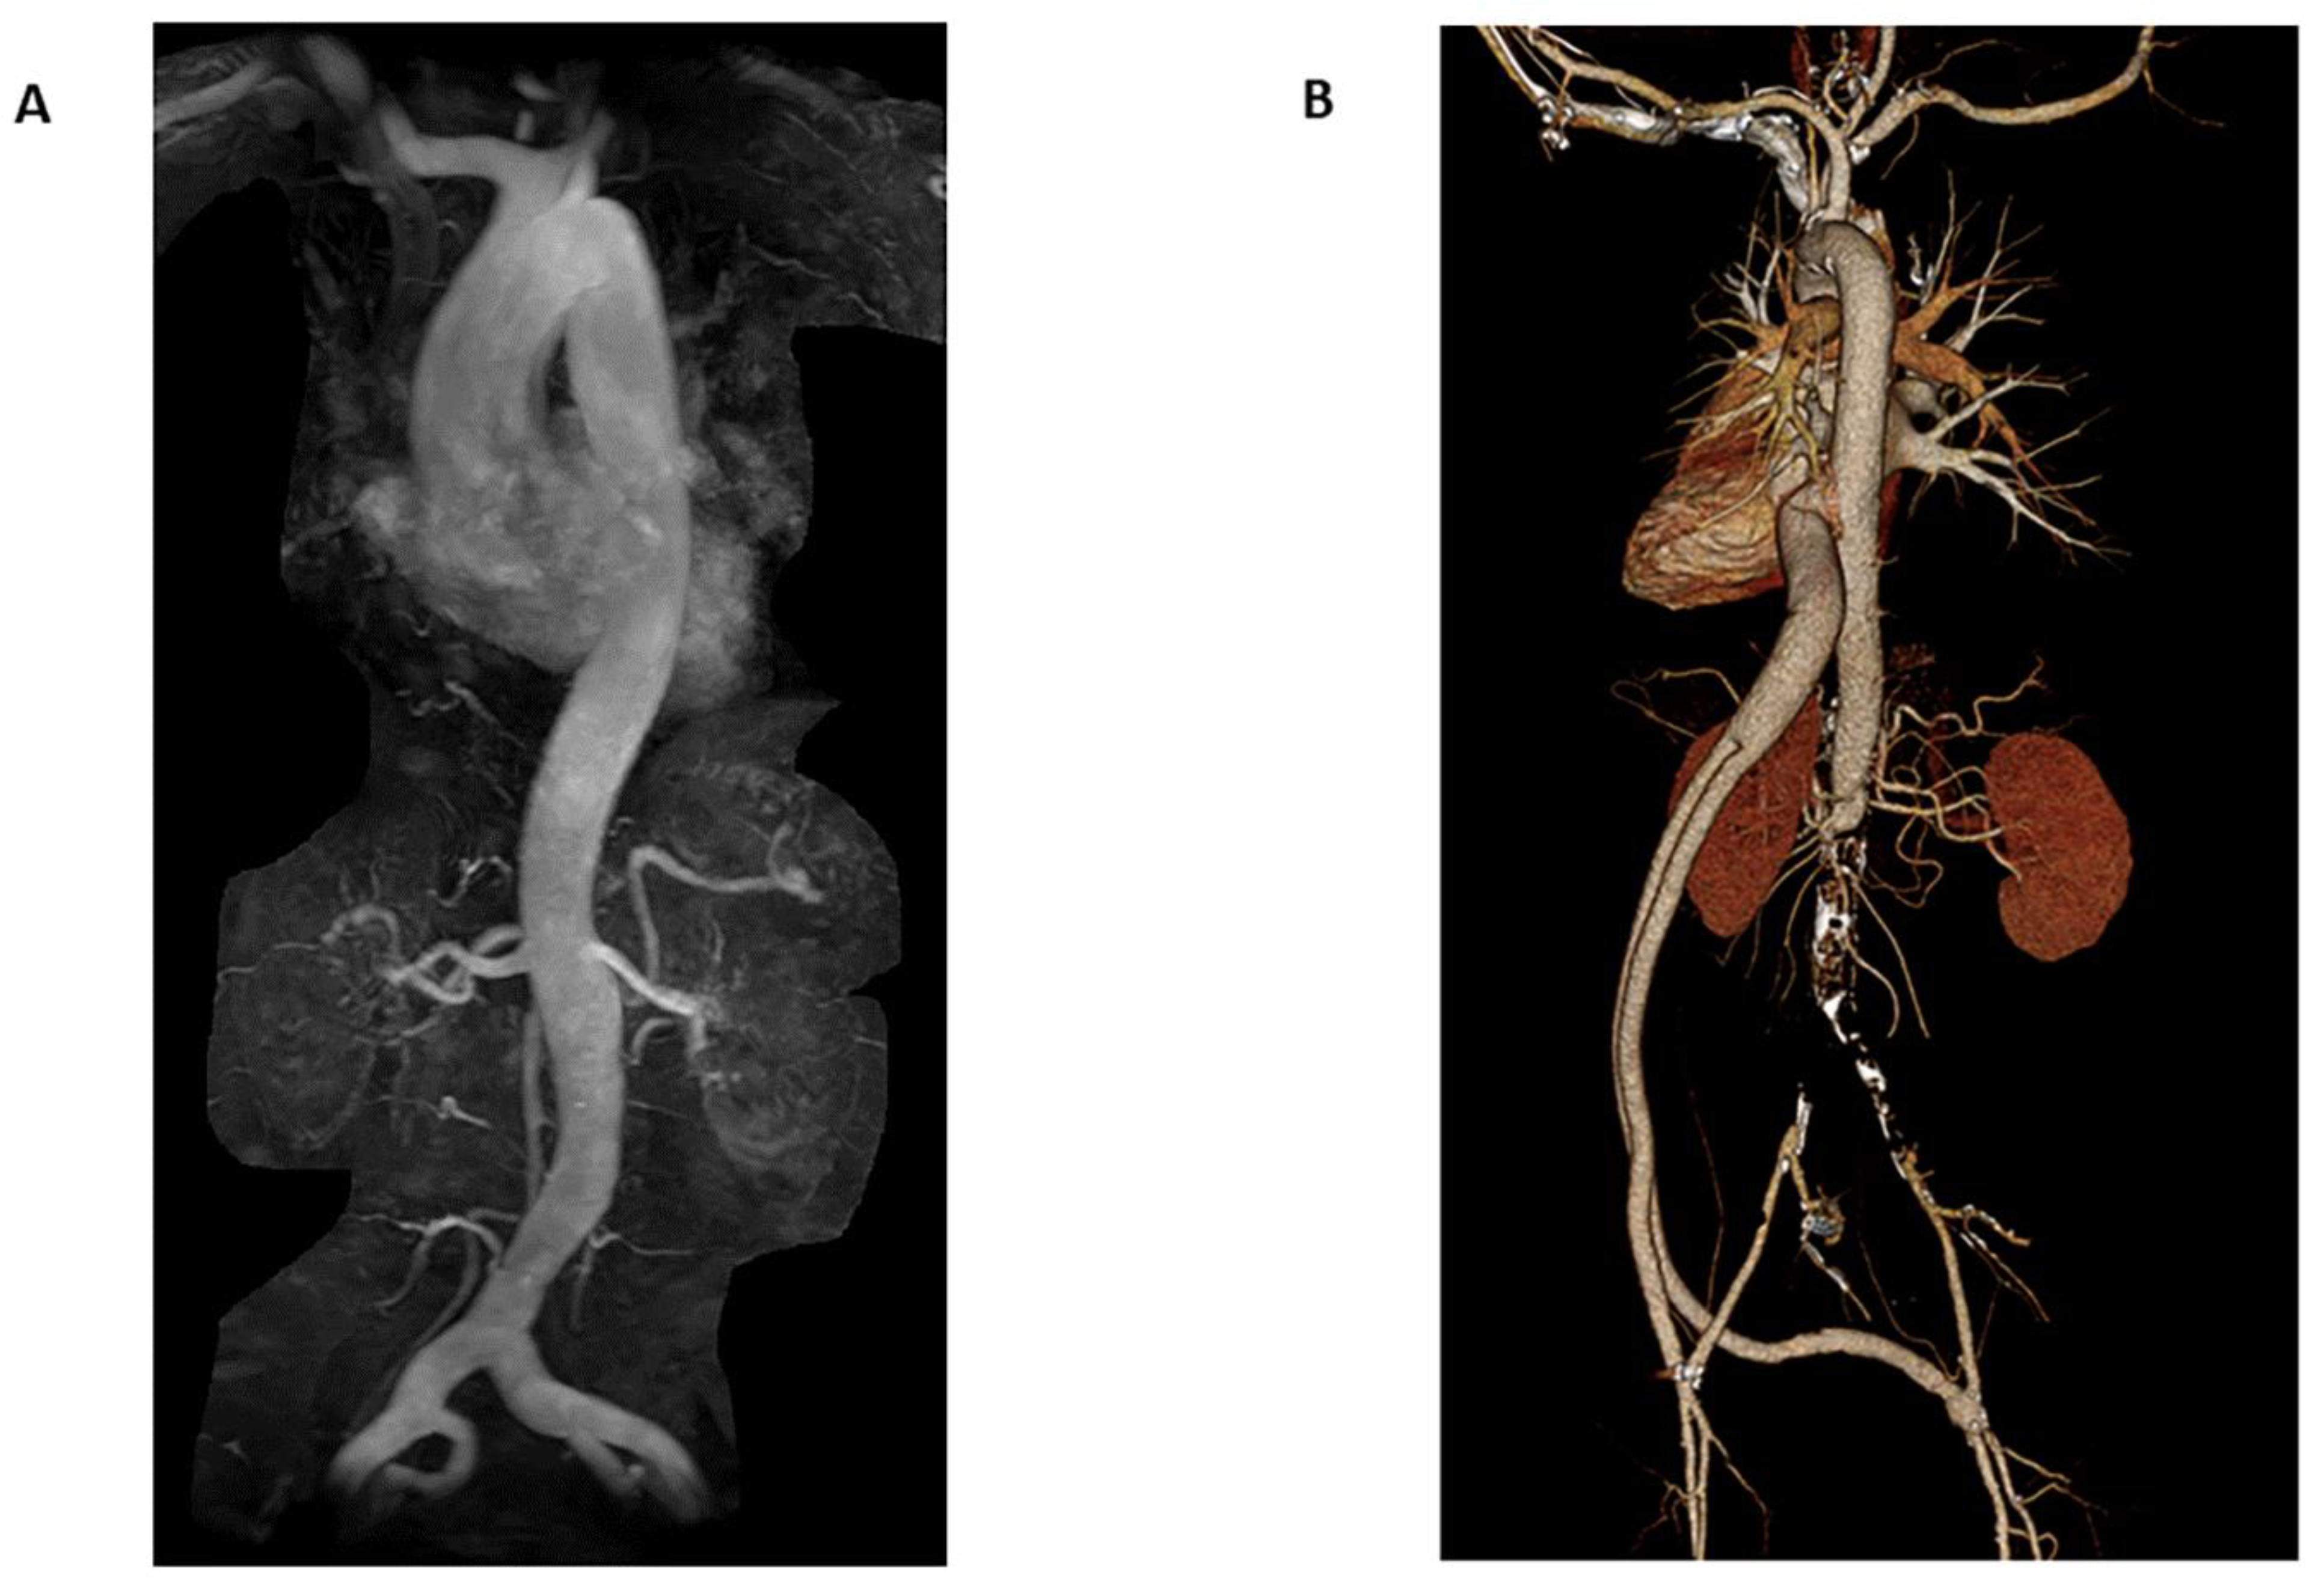

3.2. Non-Ionizing Radiation Imaging Modalities

3.2.1. Magnetic Resonance Angiography

3.3.1. Alternating Imaging Modalities